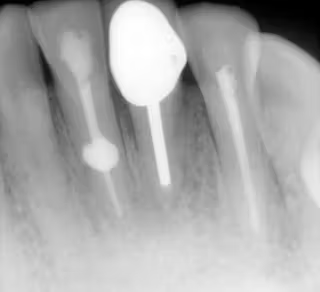

Question 1: What materials cannot be seen in the print of the X ray?

Question2: Which surface shows overhang?

Question 3: Which option is not evident on the print of the X ray?

Question 4: Which options cannot be seen in the print of the X ray?

Question 5: What options cannot be selected for tooth # 4.6?

Question 6: What options cannot be seen in the print of the X ray?

Question 7: What option cannot be identified on the print of the X ray?

Question 8: What condition can be seen in the X ray?

Question 9: Which option cannot be seen in the lower jaw?

Question 10: Which option can be selected for the following X ray?

Question 11: Which materials cannot be seen in the print of the X ray?

Question 12: What option cannot be selected for the following X ray?

Question 13: What option cannot be selected for the following X ray?

Question 14: Which surface shows overhang restoration?

Question 15: Which surface shows overhang in the restoration?

Question 16: Which surface shows overhang?

Question 17: Which surface shows overhang?

Question 18: Which surface shows overhang?

Question 19: Which option can be chosen for the tooth # 3.6?

Question 20: which tooth shows defective resotration?

Question 21: What option is can be selected for distal tooth # 4.6?

Question 22: Which surface shows defective restoration?

Question 23: Which surface shows overhang?

Question 24: Which surface shows defective restoration?

Question 25: Which surface shows open margin?